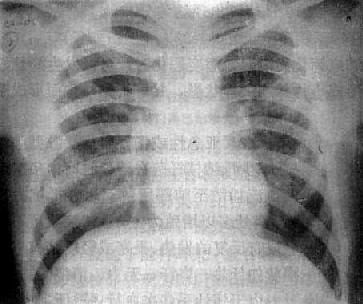

慢性血行播散型肺结核

图3-1-23 慢性血行播散型肺结核

两肺野布满大小不一、密度不同、分布不均的病灶,

下野较少,膈位置低而平